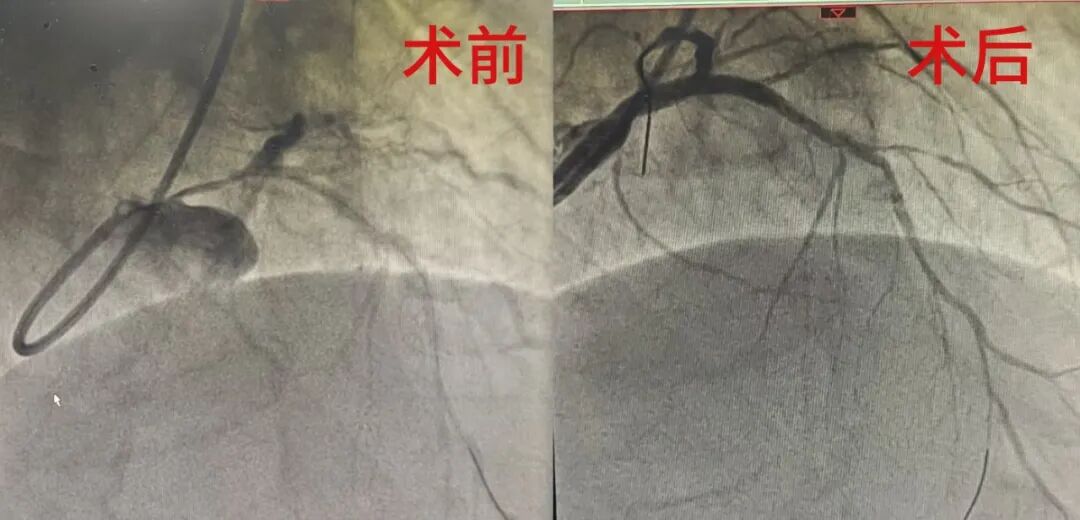

经朋友推荐,周先生慕名找到青岛大学附属日照医院/日照心脏病医院副院长、心内科第一主诊组唐忠仁主任。入院后进一步检查发现,病情比预想更为棘手:不仅有严重的左主干病变、回旋支分叉病变,前降支和右冠这两条关键血管也完全闭塞且伴有严重钙化——这些都是冠脉介入治疗中公认的“硬骨头”。综合考虑患者年龄不算大,以及介入治疗的强烈意愿,心内科第一主诊组在经过多学科讨论,评估患者心功能后,决定为他奋力一试。

术中,在血管内超声的精准引导下,唐忠仁主任团队精细操作导管、导丝、球囊,在极度狭窄的血管中“精雕细琢”,最终成功打通堵塞血管。

如果说周先生的病情是“复杂”,55岁的许先生则堪称“凶险”。他因突发胸闷气短被紧急送医,冠脉造影结果令人揪心:左主干全程病变,最狭窄处堵塞高达95%,血流仅能“挤过针眼”般艰难流动。

当硬核技术遇上患者的信任,每一份托付都掷地有声。在IVUS指导下,当左主干至前降支处成功植入支架,瞬间打通堵塞血管、恢复血流,将许先生从死亡线上拉了回来。